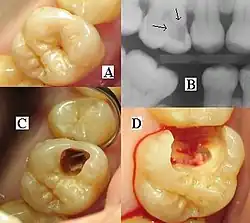

B) Röntgenologische Diagnostik

C) Eröffnung der Kavität

D) Caries profunda mit Eröffnung der Pulpa

Caries profunda

Bei der Caries profunda (lat. tiefe Zahnkaries) ist die Kariesläsion bis über 2/3 der Dentinschicht in Richtung der Pulpa vorgedrungen. Die Läsion besteht dann

- aus der Destruktionsschicht, in der Bakterien nicht nur Mineral aufgelöst, sondern auch die Proteinmatrix zersetzt haben,

- der Zone der bakteriellen Penetration, in der Bakterien in die Dentinkanälchen eingedrungen sind,

- der Demineralisationszone (Mineralverlust durch Säureeinwirkung)

- und der Transparenzzone. In dieser haben die Odontoblasten mehr Mineral in den Dentinkanälchen abgelagert, um den Fortschritt der Karies zu verzögern. Im mikroskopischen Dünnschliff erscheint diese Schicht durchsichtig, da die optischen Grenzflächen (mineralisiertes Dentin und Kanalinhalt) wegen der Mineralablagerung verschwunden sind.

Caries penetrans

Bei der Caries penetrans (durchdringende Zahnfäule) hat der Defekt durch das Dentin hindurch die Pulpa (im Volksmund: „Zahnnerv“) erreicht, so dass eine Verbindung zwischen Mundhöhle und Pulpencavum (Hohlraum, in dem sich die Pulpa befindet) entstanden ist.